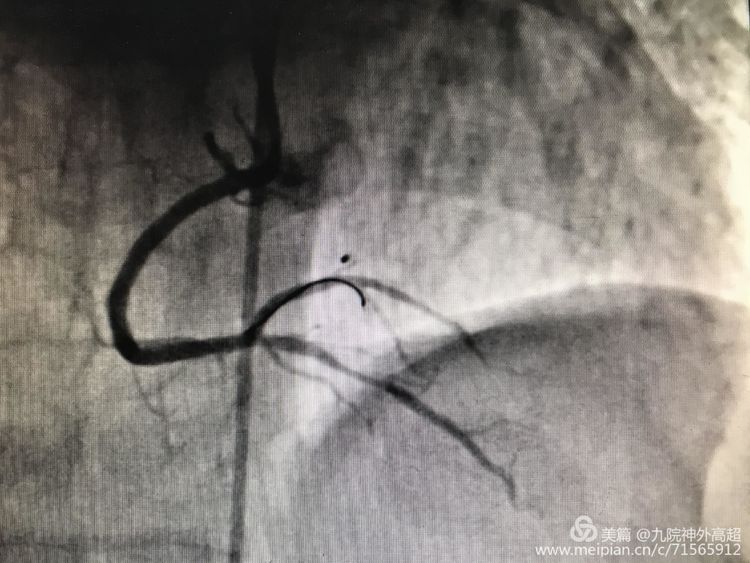

RAC近端、中段狭窄90%

RAC支架置入,狭窄消失